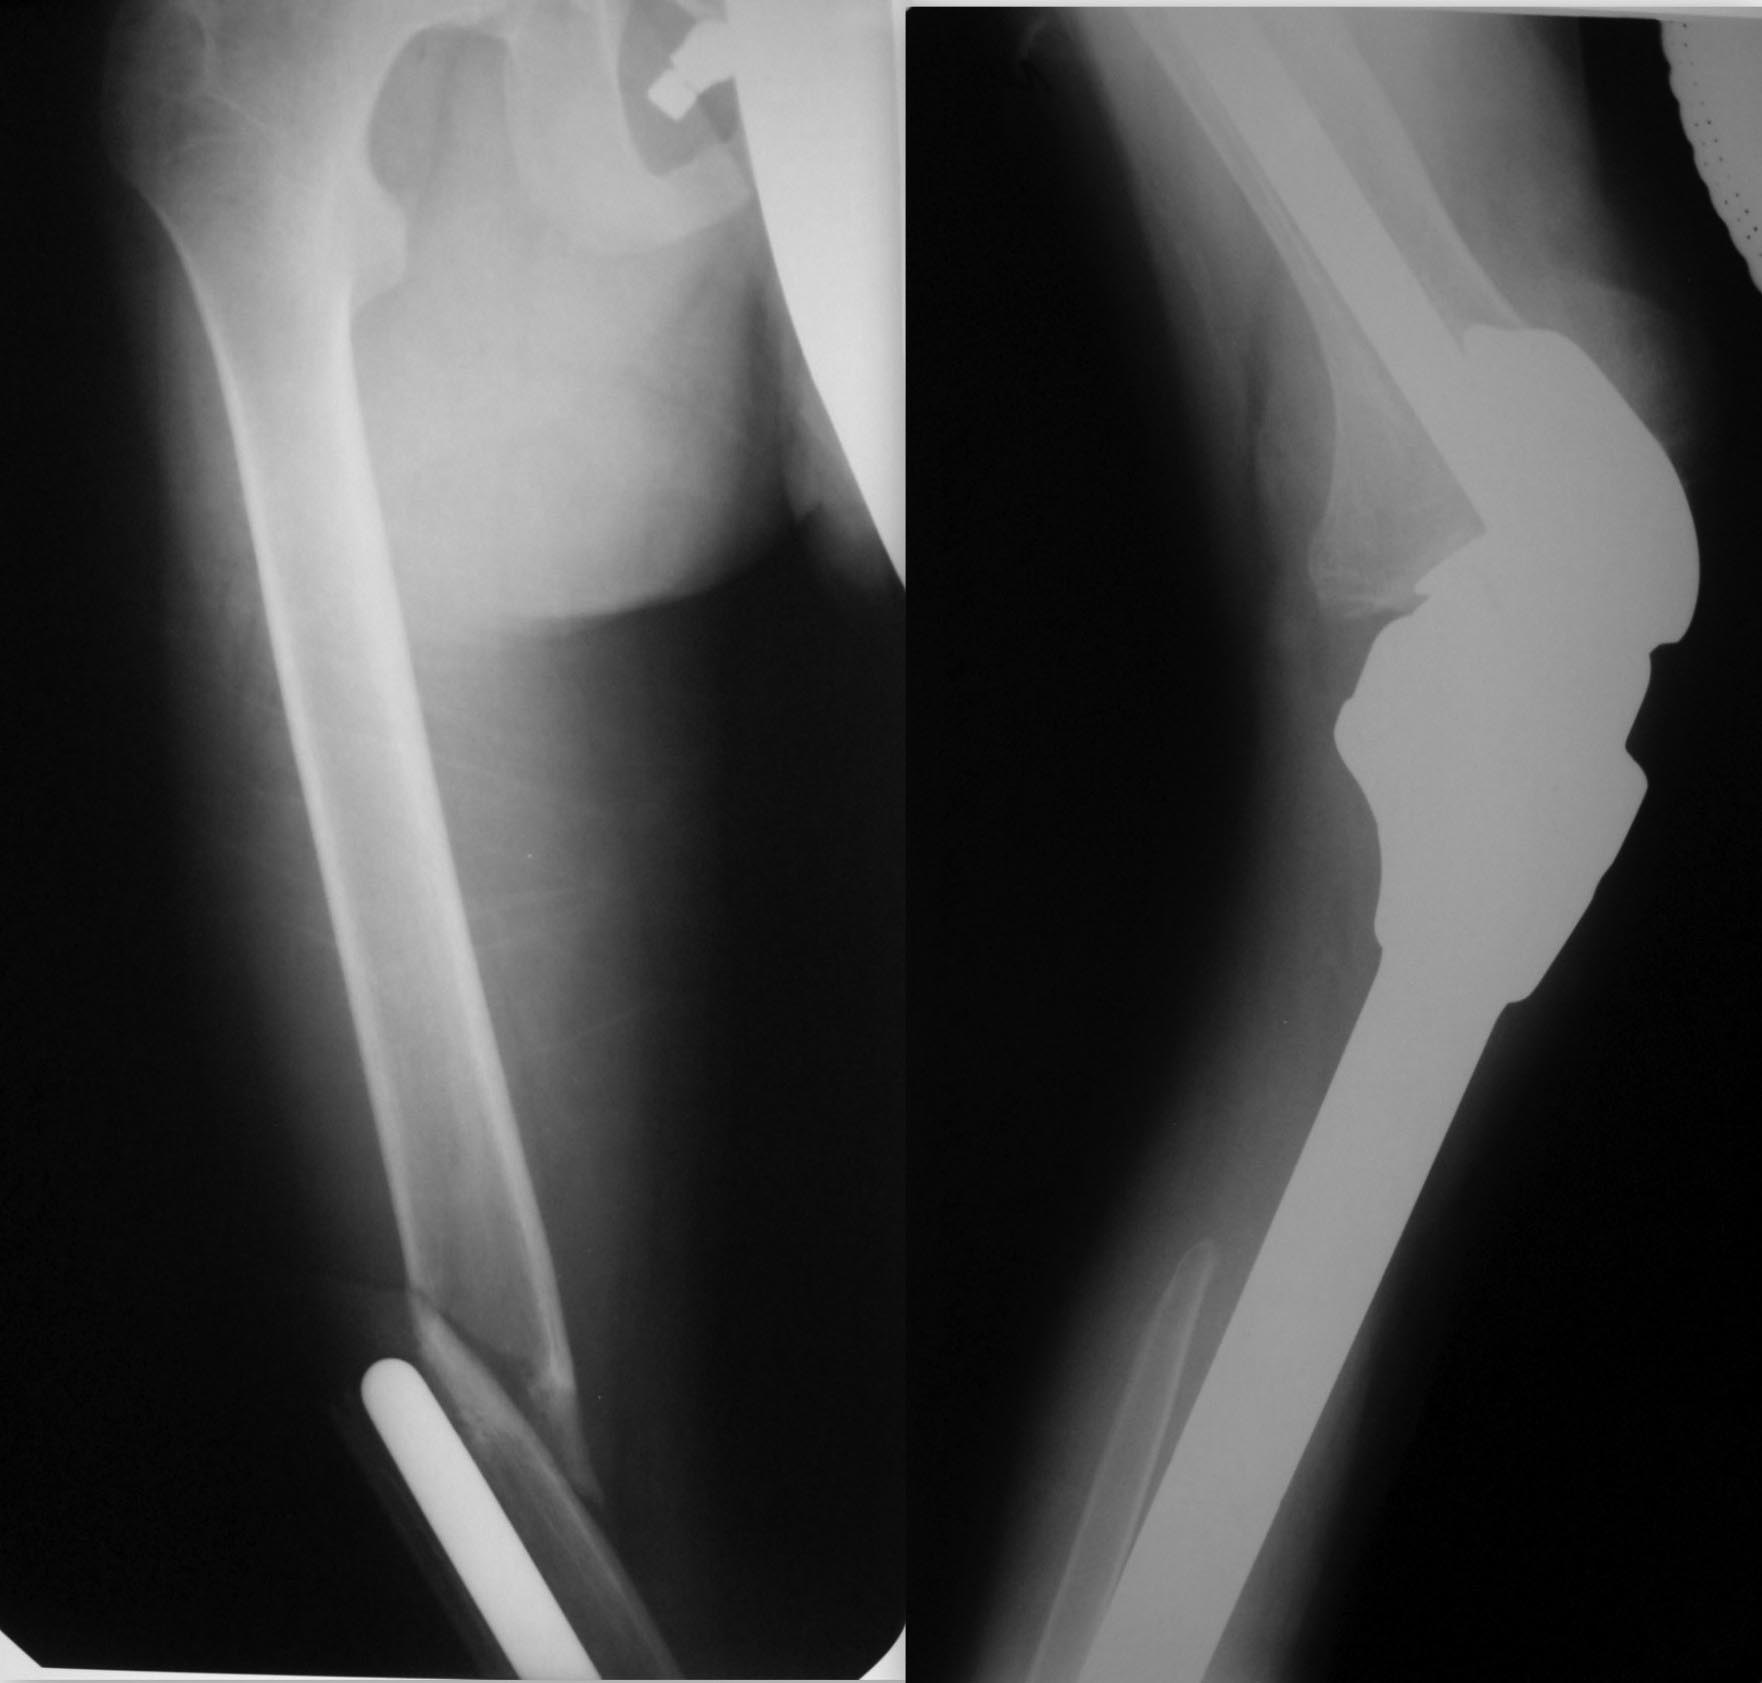

Здравствуйте, уважаемые коллеги. Нужен Ваш совет. 15-летний подросток. В

возрасте 14 лет выявлена остеогенная саркома большеберцовой кости, после

предварительного курса ПХТ оперирован в феврале 2016 г. в столичной

клинике, выполнена резекция костей голени с

опухолью, эндопротезирование коленного сустава.

3 дня назад - травма - подвернул ногу, упал. Имеем перелом бедра на

уровне проксимального штифта протеза. Учитывая, что с эндопротезами мы

дело в детском отделении не имеем, опыта лечения подобных больных нет.

Связывались с отделением, где ребёнка оперировали, там посоветовали

коксит на 2-3 месяца.

Но... 1. Подобный перелом удержать в коксите - более чем непростая

задача, да и понадобится, наверное, не 2-3 месяца. 2. Хочется всё-таки

мобилизовать ребёнка, он и так уже 2 с лишним года лечился от более чем

серьёзной болезни, ходил на костылях. В связи с чем прошу совета, как

быть. Оставить всё-таки в коксите? Оперировать? Если да, то чем? В

наличии - аппарат Илизарова, стержневые аппараты, пластины без УС,

детские блокированные гвозди Остеомед.

Собственные мысли - купим длинную пластину с угловой стабильностью,

постараемся провести шурупы мимо ножки эндопротеза. Либо комбинированный

спице-стержневой аппарат опять-таки, спицы вне ножки протеза. Хотелось

бы узнать мнения более опытных коллег.